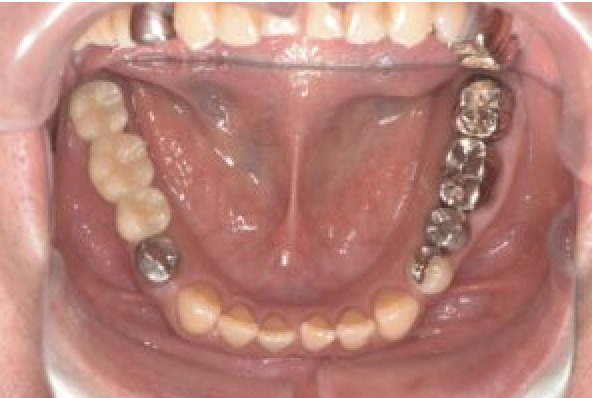

| 備考 | 右上の欠損部へのインプラントを希望で来院されました。 左下のブリッジの下にものが挟まりやすいとのことでブリッジ部分もインプラント埋入を希望されました。口腔内の銀歯も全て綺麗にやりかえたいとのことで、ダイレクトボンディングやセラミックインレーやジルコニアクラウンでやりかえていきました。 右上6番のインプラント埋入時にはソケットリフトで骨造成を行なっています。 見た目だけではなく噛みやすくなりとても満足されています。現在はエアフローのクリーニングやホワイトニングで通院されています。 |